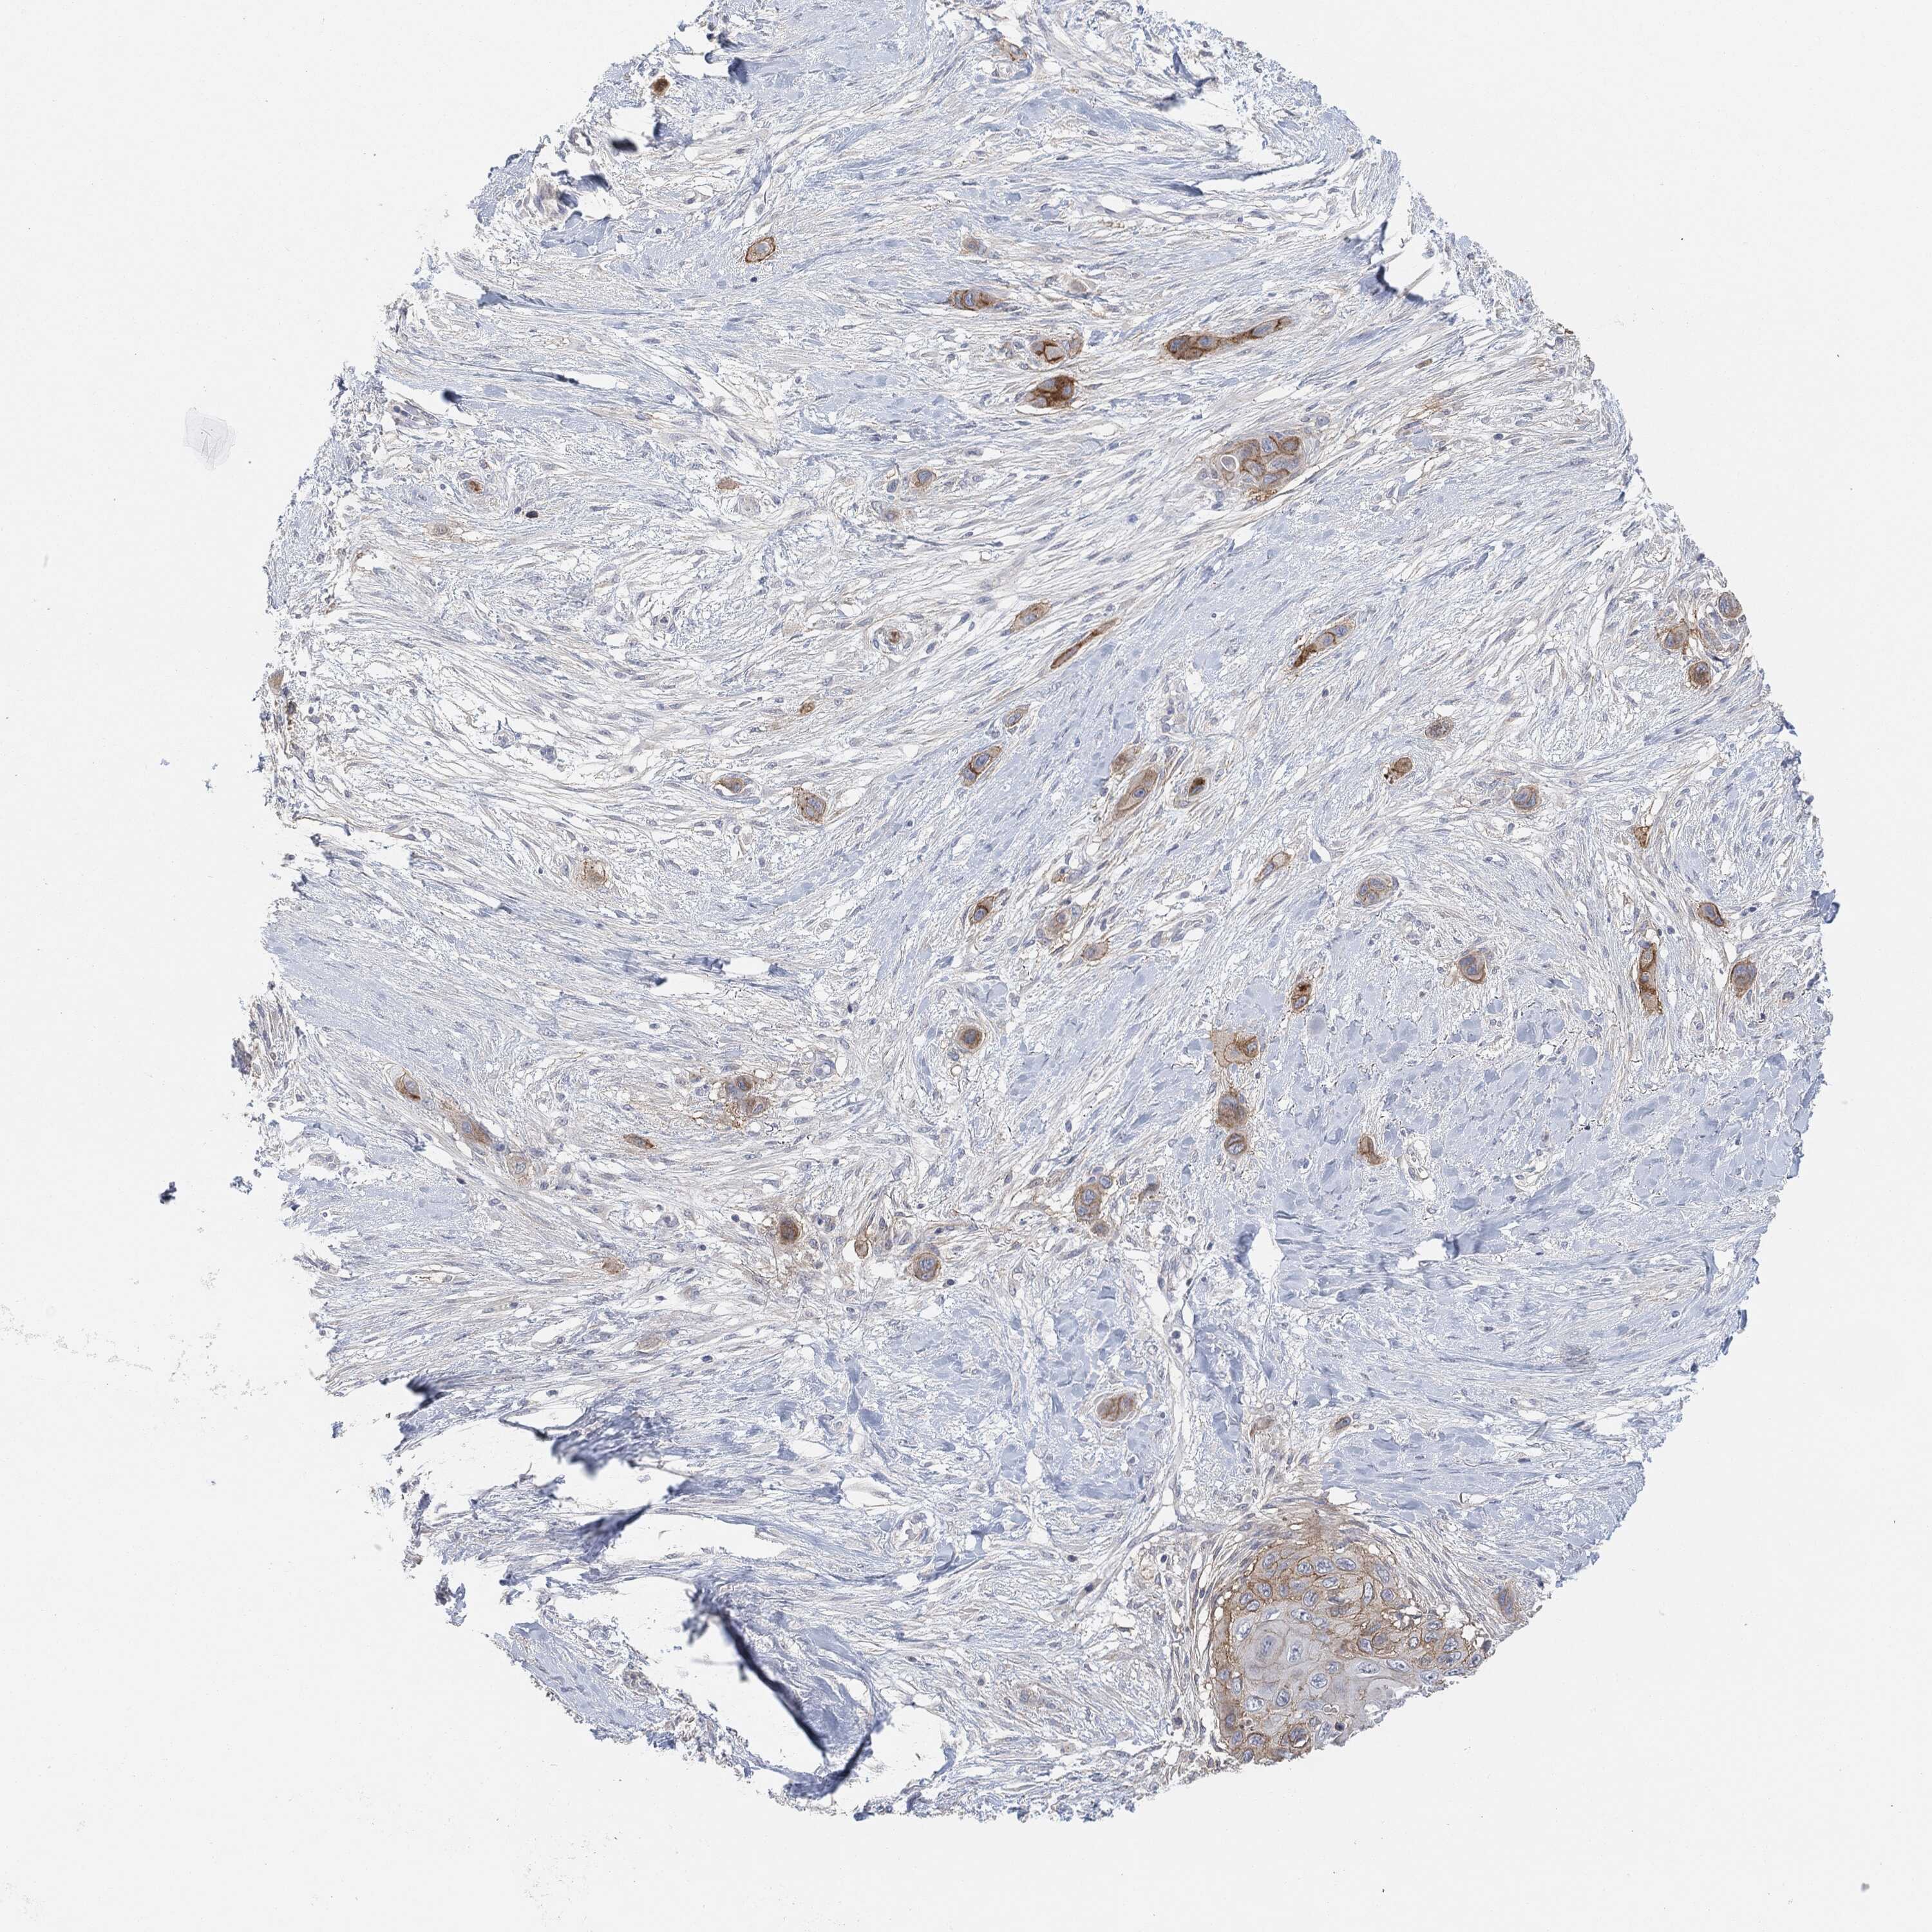

SKIN CANCER - Protein expressioni

A mouse-over function shows sample information and annotation data. Click on an image to view it in a full screen mode. Samples can be filtered based on level of antibody staining by selecting one or several of the following categories: high, medium, low and not detected. The assay and annotation is described here.

Antibody stainingi

Antibody staining in the annotated cell types in the current human tissue is reported as not detected, low, medium, or high, based on conventional immunohistochemistry profiling in selected tissues. This score is based on the combination of the staining intensity and fraction of stained cells.

Each image is clickable and will lead to virtual microscopy that enables deeper exploration of all samples and also displays staining intensity scores, fraction scores and subcellular localization as well as patient and tissue information for each sample.

Squamous cell carcinoma, NOS